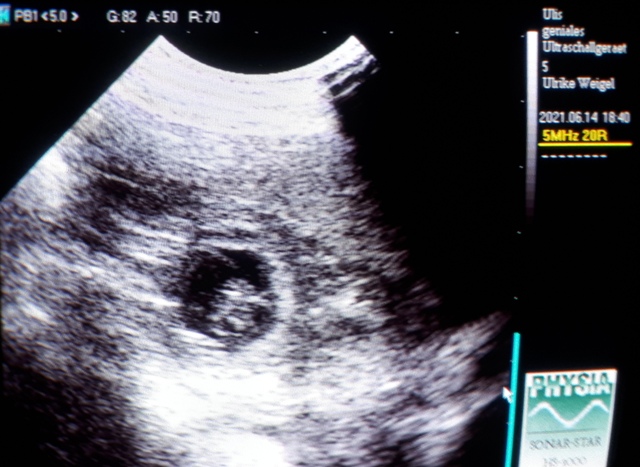

Der Ultraschall war so schön, Melli und ich konnten einige Lillis sehen :)

Herrlich!

Zählen unmöglich, ein normaler Wurf denke ich...

Das wird Überraschung bleiben!

Das Fotomachen war schwierig: Phoebe kraulen, schallen und knipsen war zu viel!

Immer wenn wir mal 3 gleichzeitig drauf hatten, war ein Atemzug später wieder alles weg ;)

Bin halt ein Laie, aber es geht ja auch nur darum zu wissen:

Juhuuu!!! Wir sind trächtig :) :)

Nun sind sie Realität, das ist sooo schön!

14.06.2021 - 26. Tag der Trächtigkeit

Heute geht es Phoebe viel besser!

Wir haben nochmal nachgeschaut :)

Unsere Lillis entwickeln sich prächtig und sind ganz schön gewachsen:

Wie ihr vielleicht erkennen könnt, gehen direkt neben der kleinen Furchthülle, beim

weiterführen des Schallkopfs, die nächsten Fruchthüllen auf (..links..)

Man kann ein Teil der Nabelschnur und im Hintergrund den Welpen erkennen.

Hier sieht man einen anderen Zwerg etwas besser :)

Bis morgen :)